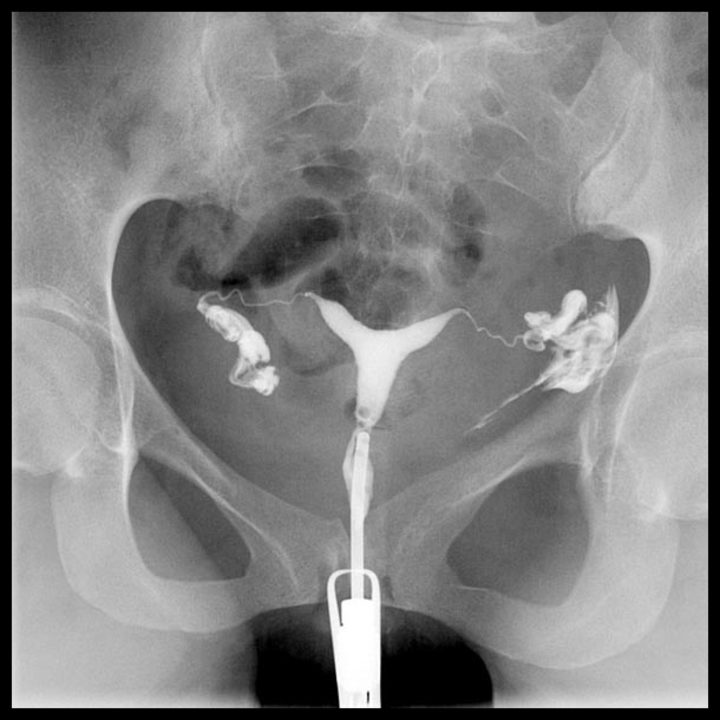

Bebek dişleri geçici olmasına rağmen, sağlıklı sabitlerin oluşması için tedavi edilmelidir. Bu bebeklere kan, idrar tetkiki, kültür testi, akciğer röntgeni ve bel suyu (lomber ponksiyon) tetkikleri yapılabilir. Röntgen ilk üç aylık dönem içerisinde çekilirse bebekte oluşum bozukluklarına neden olabilir. Genellikle rahim röntgeni (hsg) sonuçları, işlem bittikten sonra 10 ila 20 dakika sonrasında çıkar. 1 yıl satış sonrası servis: Tele (kalp röntgeni) kalp röntgeni (telekardiyogram = tele):

Rahim Filmi Nasıl Çekilir

Genellikle rahim röntgeni (hsg) sonuçları, işlem bittikten sonra 10 ila 20 dakika sonrasında çıkar. Bebek için daha güvenli ve daha rahattır. Akciğer filmi iki yönlü olarak çekilir, akciğerler önden ve yandan çekilerek çevre organlarda ve göğüs boşluğunda oluşabilecek hastalıklara da tanı.

Rahim Filmi Nasıl Çekilir

Rahim Filmi Nasıl Çekilir